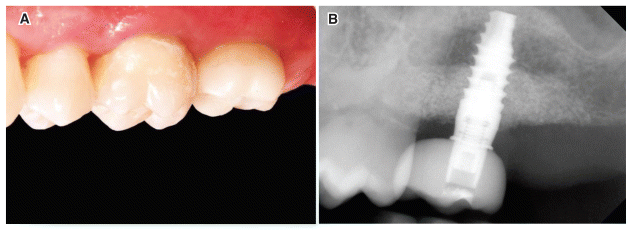

The present case report as redacted following the CARE guidelines (https://www.care-statement.org/). In January 2022, a 51-year-old male patient presented to our clinic seeking prosthetic implant rehabilitation for tooth 27, which was lost 9 years ago. The patient was classified as American Society of Anesthesiologists (ASA)-1, under the ASA Physical Status Classification System, has no significant health concerns. He was a nonsmoker and maintained a good level of oral hygiene. His medical history revealed no systemic contraindications to oral surgery. Objective and radiographic examinations showed a probing pocket depth (PPD) value of 4 mm and a clinical attachment level (CAL) of 9 mm on tooth 26. The vertical deficit of the alveolar process at site 27, measured using cone beam computer tomography (CBCT) with Romexis software (Planmeca, Helsinki, Finland), was 7 mm (Fig. 1a–b). The objective of the surgical treatment was to achieve 3D bone regeneration of the supracrestal effect at site 27 while simultaneously promoting periodontal regeneration in the distal portion of tooth 26. Additionally, qualitative and quantitative restorations of the thickness of the atrophic supracrestal soft tissue were planned to achieve the optimal biological width around the implant. A two-stage surgical and regenerative treatment was proposed; the first stage aimed to regenerate the supracrestal hard tissue while addressing the periodontal defect affecting the adjacent natural tooth, while the second surgery involved the removal of the nonresorbable devices, implant insertion, and enhancement of the supracrestal soft tissue using the connective tissue graft (CTG) technique. A virtual case resolution project was developed using 3D processing software according to there generation and guided prosthetic implantology guidelines.5 The patient was informed about the study and the collection of data and images related to his case. A signed informed consent form was obtained from the patient according to ethical standards.